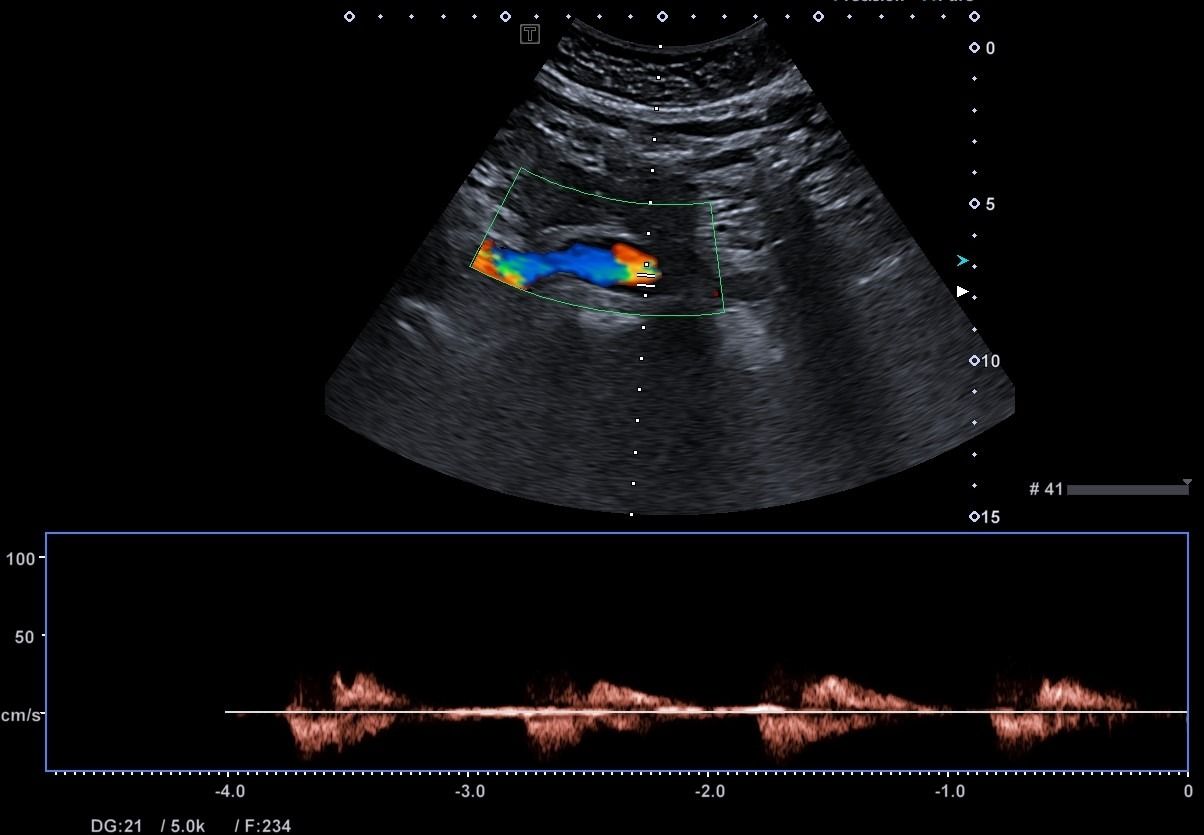

- Αιμοδυναμικές Διαταραχές: Mε τη χρήση του Έγχρωμου και του Παλμικού Doppler μπορούν να μελετηθούν οι ταχύτητες της αιματικής ροής και να ανιχνευθούν πιθανές αιμοδυναμικές διαταραχές.

- Αγγειακή Στένωση: Η αξιολόγηση της αιματικής ροής μπορεί να οδηγήσει στη διάγνωση στένωσης των αγγείων και να υπολογιστεί ο βαθμός της στένωσης.